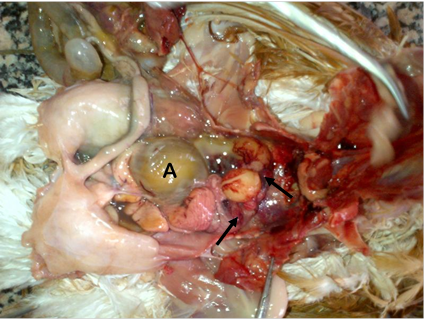

Histopathological changes in the liver, kidney, heart and spleen of affected layers are as shown in Table 2 and Figures 2‒5. The photomicrograph of the liver showed vacuolation and organisms within the central veins and sinusoids (Figure 2). There were interstitial cellular infiltration of the kidneys (Figure 3) and heart (Figure 4) with abscess around the splenic artery and lymphoid depletion in the spleen (Figure 5). Table 2 showed that 33.33% of the examined liver had fibrinous exudation and cytoplasmic vacoulation. Abscess was found in all (100.00%) of the liver, kidneys and heart while 66.67% of the examined spleen had abscess formation and fibrinous exudation. All the kidneys (100.00%) that were examined had cellular infiltration while about 33.33% of the hearts had cellular infiltration and perivascular oedema, respectively. All the spleen (100.00%) had perivascular oedema.

Figure 5 The photomicrograph of the spleen of a pullet diagnosed of mixed bacterial infection on a layer flock in Masaka, Nasarawa State, Nigeria. Note the abscess around the splenic artery (arrow) and the lymphoid depletion (D). H & Ex265.